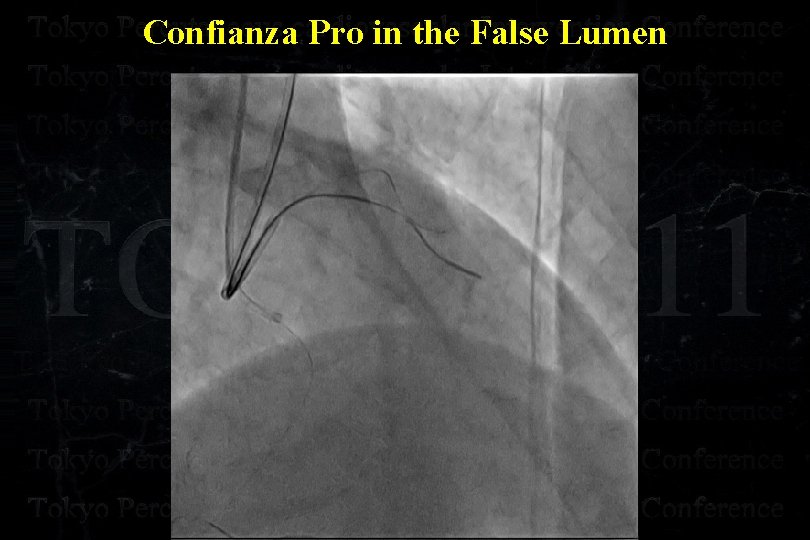

Confianza Pro in the False Lumen